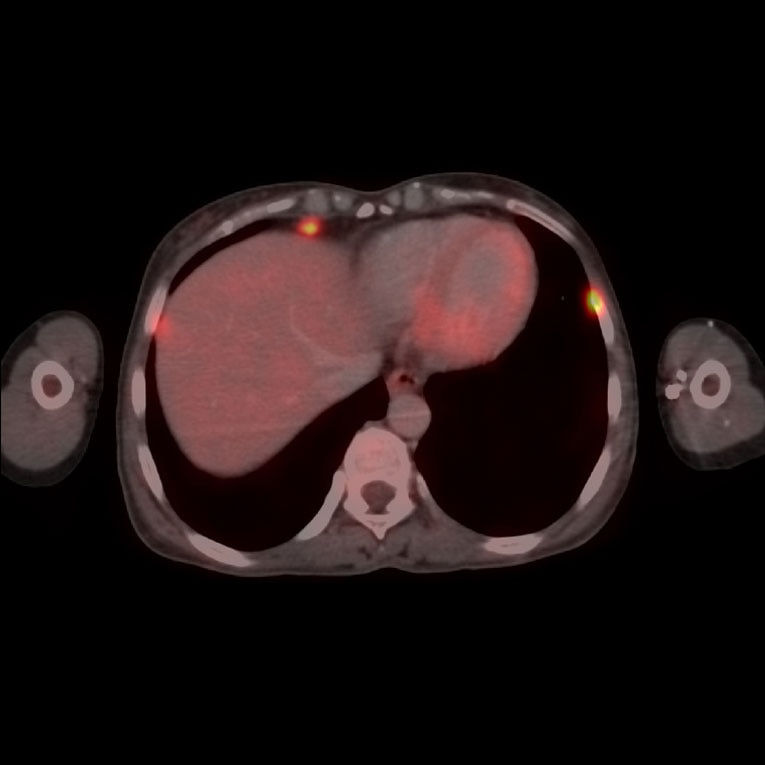

Discovery™ IQ Gen 2

Experience up to 2x improvement in image quality (SNR),⁵ and up to 67% improvement in PET/CT lesion volume measurements.⁶